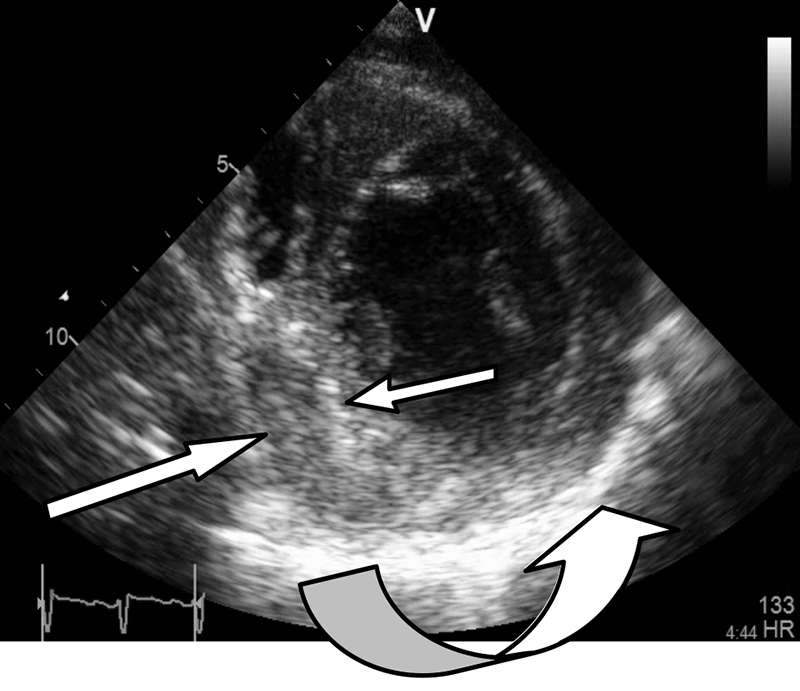

Figure 5: Short axis view showing a thickened hyper-echoic pericardium especially between 4 and 7 o’clock (curved arrow). Organised thick effusion indenting the infero-septal left ventricular wall between 6 and 9 o’clock (straight arrows)

Figure 5: Short axis view showing a thickened hyper-echoic pericardium especially between 4 and 7 o’clock (curved arrow). Organised thick effusion indenting the infero-septal left ventricular wall between 6 and 9 o’clock (straight arrows)(click to enlarge)